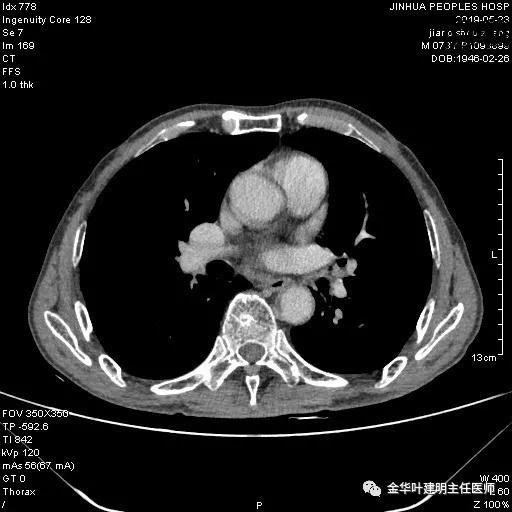

患者,男性,73岁,金华人。因“咳嗽咳痰伴胸闷2月,检查确诊左肺癌1周”入院。气管镜: 气管支气管内较多脓性分泌物,左肺上叶前段管腔新生物,局部活检、毛刷。气管镜病理:(左肺活检)鳞癌。阅胸部CT见左上叶开口处新生物,考虑需左上叶袖式切除及淋巴结清扫。具体CT表现如下:

考虑左侧大量胸腔积液,遂进一步胸部CT检查:

以上是肺窗表现,下面为纵隔窗影像: